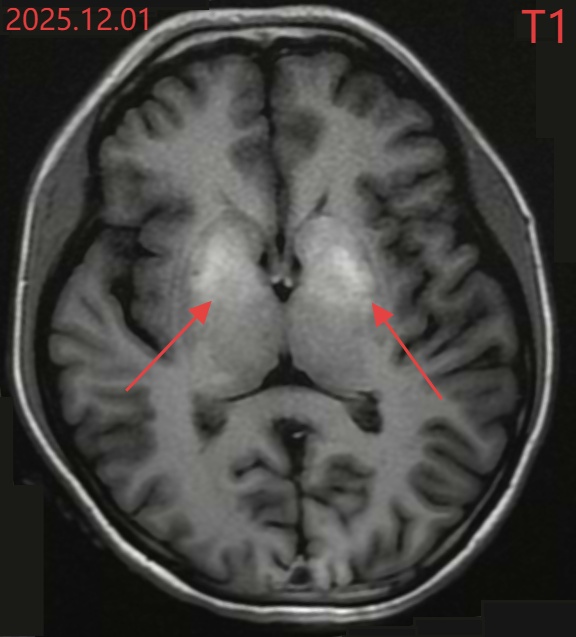

小文的颅脑MR结果

进一步的检查更令人震惊:糖化血红蛋白17.7%(正常应在6.5%以下),这意味着她的血糖在很长一段时间内都处于“失控”状态。颅脑MR显示,她大脑深处控制运动的基底节区域已经出现异常信号——这是长期高血糖对大脑的“灼伤”。